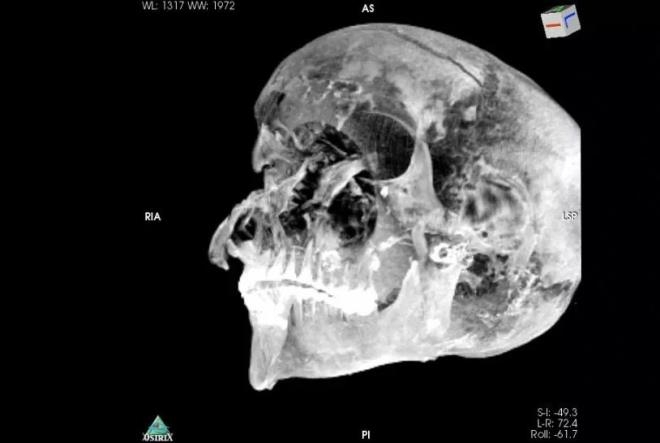

Mısır firavunu Seqenenre Tao'nun mumyası bilgisayarlı tomografiye sokuldu.